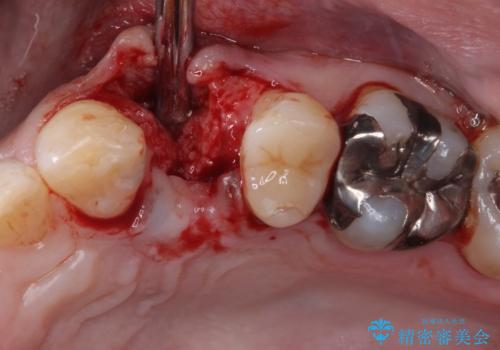

顕微鏡下で診察を行ったところ、歯根が垂直に破折していたため、抜糸してインプラントによる補綴治療を行うこととしました。

より審美的で、より機能的に優れた治療をご希望とのことであったので、ジルコニアカスタムアバットメントを用いたインプラント治療を行うこととしました。

インプラントは、人工骨を用いた際の骨誘導能が比較的高いとさせるストローマン社のSLActiveを使用しました。